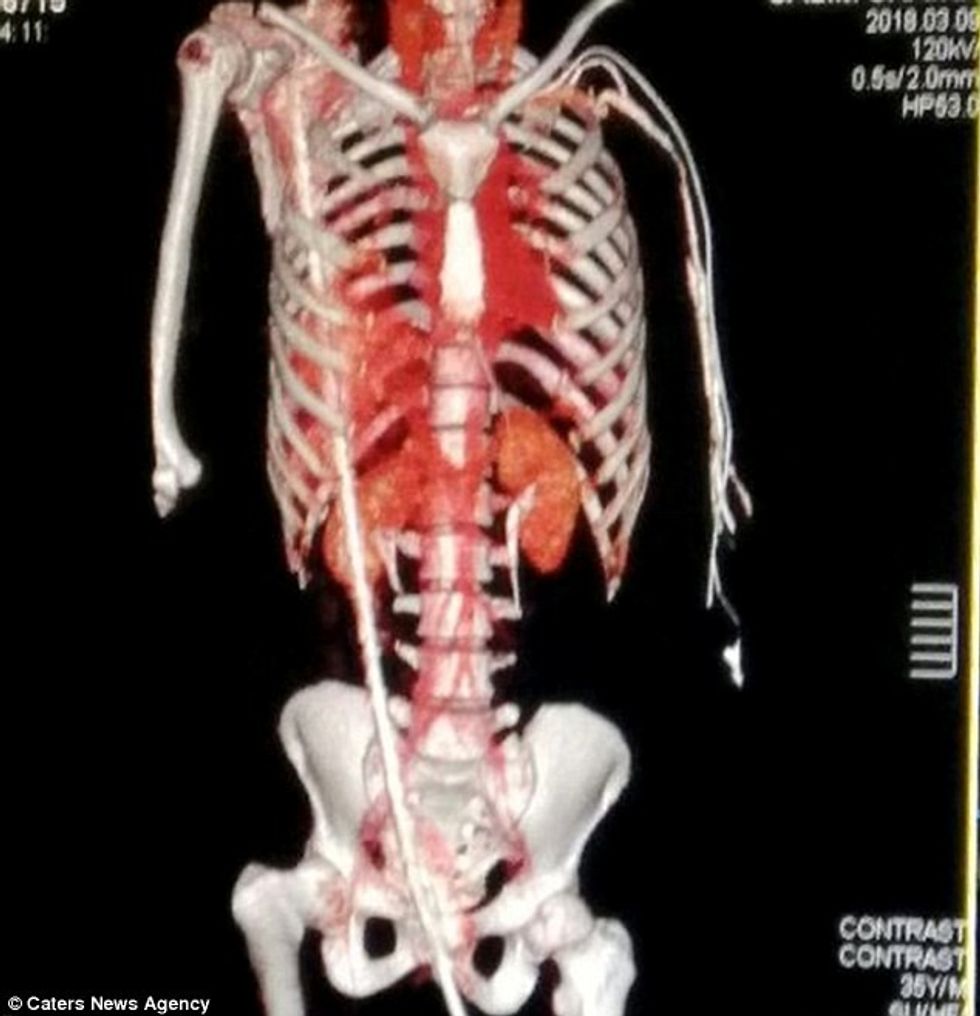

Një punëtorë ndërtimtarie është shpëtuar nga mjekët edhe pse pak kush kishte menduar se do ta mashtroj vdekjen, për faktin se një armaturë 130 centimetra e cila i është ngulur në testikuj kishte depërtuar afër qafës së tij.

Ai është dashur të duroj dhimbjen e armaturës në trup për më shumë se 165 kilometra udhëtim deri në spital. Armatura që i ishte ngulur në testikuj, kishte depërtuar në gjithë trupin dhe kishte përfunduar në qafë, duke i thyer disa kocka.

Ajo kishte depërtuar nëpër veshkë, diafragmë dhe mushkëri, por jo edhe ne zemër, dhe pas intervenimit kirurgjik 5 orësh, mjekët arritën t'i heqin nga trupi.